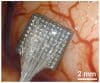

Pero cuando hablamos de interfaces cerebrales nos referimos a sistemas electrónicos que, mediante sensores implantados en el cerebro, se comunican con el sistema nervioso, que también utiliza señales eléctricas.

Existe otro tipo de interfaz, las que tienen una comunicación bidirecccional con el cerebro y registran la información pero también la envían al sistema nervioso; el objetivo es hacer posible un diálogo con el cerebro, una comunicación que sea «efectiva, robusta, fiable y segura», señala Fernández, también director del grupo de Neuroingeniería Biomédica del CIBER de Bioingeniería, Biomateriales y Nanomedicina (CIBER-BBN).

Son pasos necesarios hacia un futuro en el que «vamos a ser capaces de hacer muchas cosas que todavía hoy no son posibles», pero, hasta entonces, estas tecnologías tendrán que resolver muchos retos, como el de la biocompatibilidad porque los implantes -como con los trasplantes de órganos- son cuerpos extraños que el organismo tiene que tolerar.

Por eso, uno de los retos es buscar materiales que no se degraden y que funcionen adecuadamente durante largos periodos.